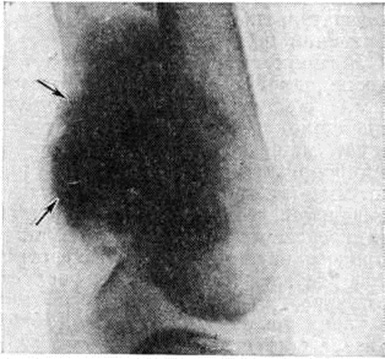

Паростальная саркомаПаростальная саркома (греческий para около + osteon кость; саркома; синонимы: оссифицирующая паростальная остеома, параоссальная саркома, паростальная остеобластическая саркома, паростальная остеогенная саркома, юкстакортикальная остеогенная саркома) — злокачественная остеогенная опухоль, развивающаяся из камбиального слоя надкостницы. Выделена из группы остеогенных сарком в 1951 год Гешиктером и Коуплендом (Ch. F. Geschickter, М. М. Copeland). Паростальная саркома встречается относительно редко, преимущественно в возрасте 30— 50 лет, несколько чаще у женщин, составляет до 3—6% всех первичных костных сарком. Опухоль чаще поражает диафизы длинных трубчатых костей, особенно часто — дистальный диафиз бедренной кости. Макроскопически образована плотными костными массами и отдельными мягкими узлами, связанными с периостом и не поражающими корковое вещество кости. По гистологический строению напоминает компактную остеому (смотри полный свод знаний), но в Паростальная саркома пространства между костными перекладинами обычно заполнены опухолевой остеогенной тканью с анаплазией различной степени. Иногда эта ткань приобретает сходство с тканью фибромы или фибросаркомы; часто в ней встречаются островки, напоминающие хондросаркому. Костное вещество опухоли имеет относительно зрелую структуру, но отличается беспорядочным расположением костных перекладин (рисунок 1). В клинические, картине многие исследователи выделяют первоначальную фазу, в течение которой опухоль медленно растёт без выраженных проявлений. Боль, как правило, отсутствует или бывает умеренной. Когда опухоль достигает значительных размеров, появляются симптомы, связанные со сдавлением нервных стволов и кровеносных сосудов, появляются боли, которые усиливаются и становятся постоянными. Рентгенологические картина в начальных стадиях развития опухоли характеризуется наличием в мягких тканях вблизи кости солитарного, грибовидной формы, чётко отграниченного плотного опухолевого образования (рисунок 2). У его полюсов между опухолью и корковым веществом подлежащей кости видна линия просветления. В дальнейшем кость окутывают наподобие муфты опухолевые массы с отчётливыми очертаниями, состоящие как бы из сливающихся шаров и полушарий различных размеров. Структура опухоли в центральной её части плотнее, однороднее, чем в периферической. Периостальной реакции не наблюдается. Паростальная саркома метастазирует гематогенно в лёгкие, где метастазы могут быть обнаружены при рентгенологическое исследовании.